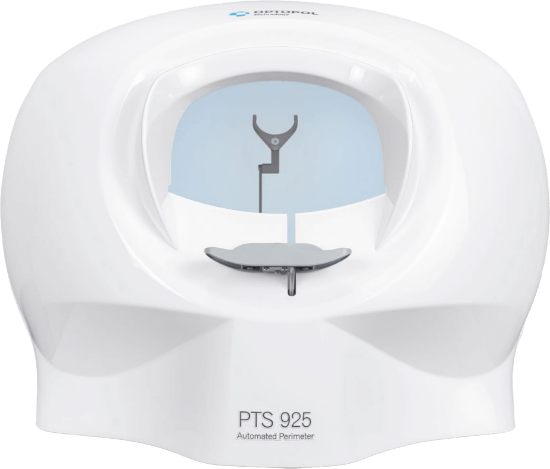

PTS 925W

The PTS 925W is our compact perimeter that packs a punch. It provides everything you need in our smallest footprint.

Key Features:

-

New 24-2C pattern now available

-

Goldman III

-

Voice Guidance

-

ZETA™, ZETA™ FAST, and ZETA™ Faster

-

DPA™ Defect Progression Analysis

FAST THRESHOLDING

Using ZETA™ thresholding algorithms, test your patients in under 3 minutes.

EYE TRACKING

Monitor patient pupil movement during examination.

BLINK DETECTION

Our software detects when the eye is closed, and will not present stimuli to the patient.

HEAD TRACKING

Live monitoring and automated adjustments throughout exams.

DPA™ DEFECT PROGRESSION ANALYSIS

Create a baseline and follow disease progression over time.

EYESEE™

In the review screen, click on any point during the exam to see the eye position reviewing the test result.

VOICE GUIDE

Voice messages assist operator and patient during the examination.